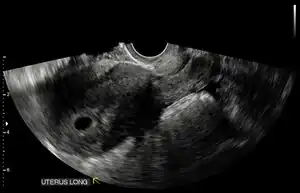

Ultrasound

Obstetric ultrasonography may also be used to detect and diagnose pregnancy. It is very common to have a positive at home urine pregnancy test before an ultrasound. Both abdominal and vaginal ultrasound may be used, but vaginal ultrasound allows for earlier visualization of the pregnancy. With obstetric ultrasonography the gestational sac (intrauterine fluid collection) can be visualized at 4.5 to 5 weeks gestation, the yolk sac at 5 to 6 weeks gestation, and fetal pole at 5.5 to 6 weeks gestation. Ultrasound is used to diagnose multiple gestation.[3][19]

Ultrasound is also a common tool for determining viability and location of a pregnancy. Serial ultrasound may be used to identify non-viable pregnancies, as pregnancies that do not grow in size or develop expected structural findings on repeated ultrasounds over a 1-2 week interval may be identified as abnormal.[34] Occasionally, a single ultrasound may be used to identify a pregnancy as non-viable; for example, an embryo that is greater than a certain size but that lacks a visible heart beat may be confidently determined to be not viable without the need for follow up ultrasound for confirmation.[34]